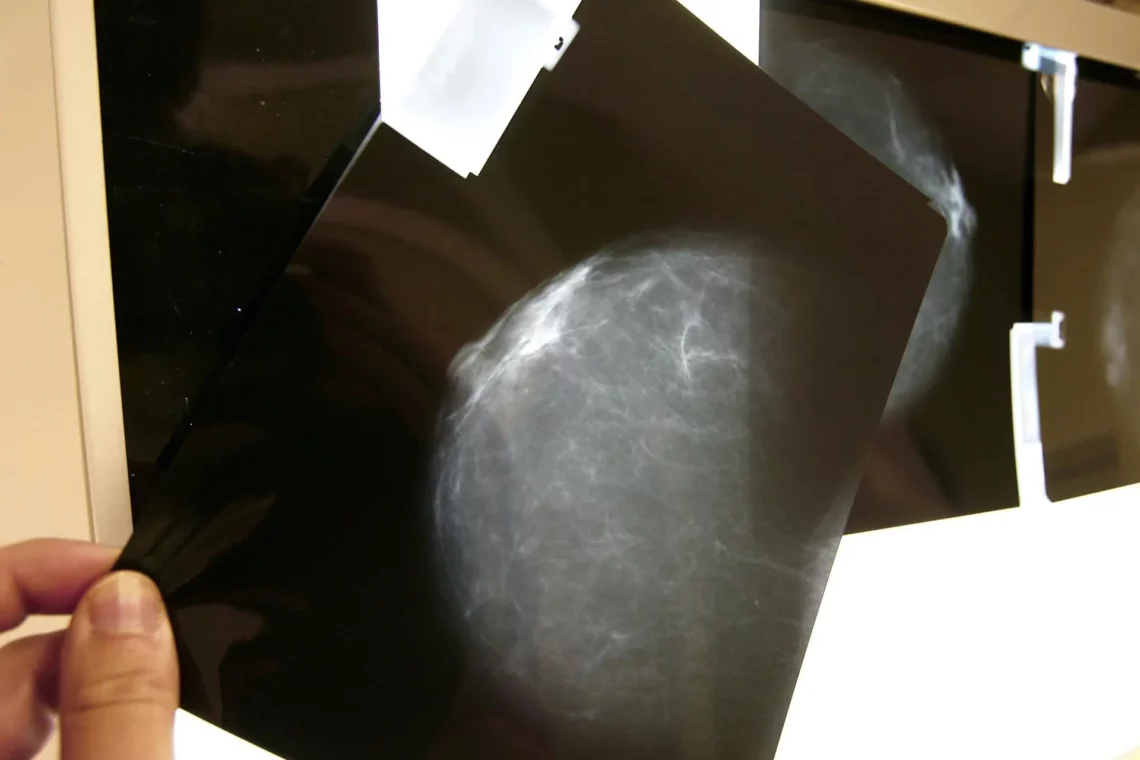

Según ha explicado este lunes el hospital barcelonés en un comunicado, el DCIS es un cáncer de mama no invasivo o preinvasivo que se inicia en los conductos lácteos, que aunque no es potencialmente mortal aumenta el riesgo de padecer uno de mayor gravedad más adelante.

Los investigadores analizaron muestras de pacientes que se habían sometido a cirugía para extirpar el DCIS e identificaron 812 genes asociados con la progresión del cáncer durante los próximos cinco años de vida del enfermo y desarrollaron un clasificador de estas personas.